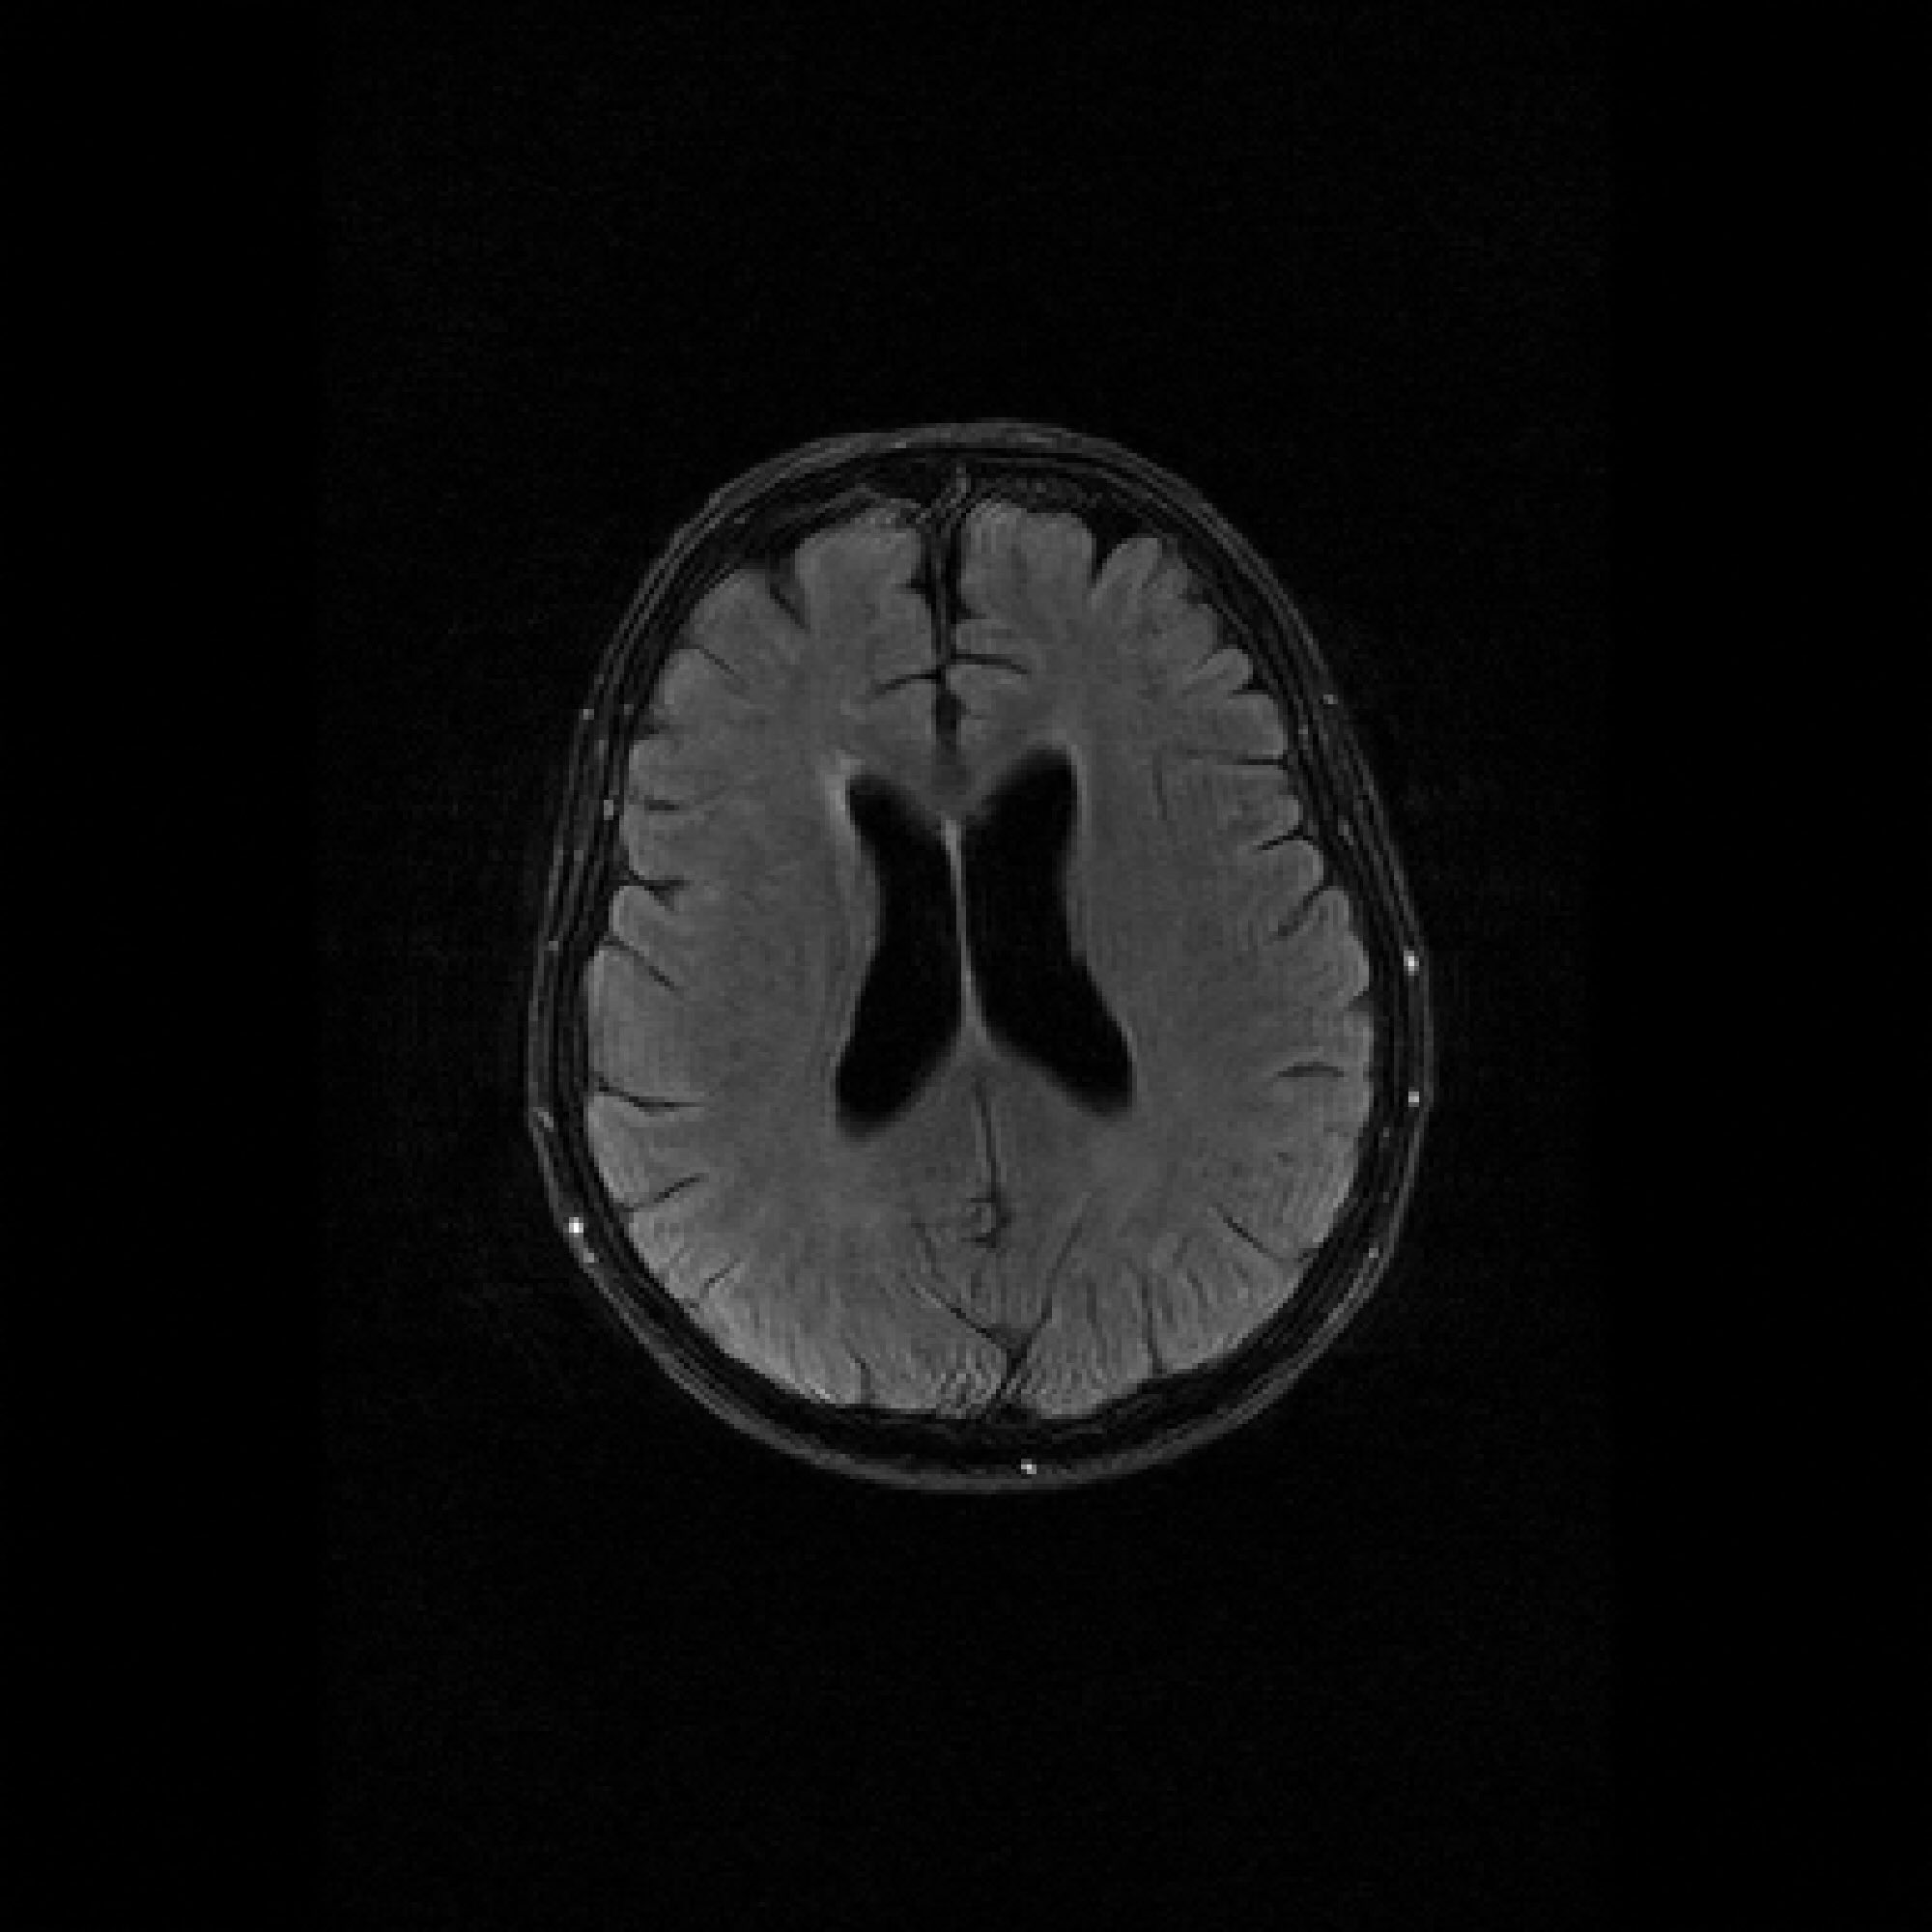

Refer to caption

Figure 3: Pixel-wise standard deviations of reconstructions across 10 random k-space sampling masks (R=7R=7) of the same slice. Top to Bottom: models trained on 100, 500, and 1000 slices. PaDIS-MRI consistently exhibits lower pixel-wise variance (fewer bright regions) than FastMRI-EDM across training sizes and contrast types, indicating more stable reconstruction.

We assess reconstruction consistency by evaluating variability across 10 random k-space undersampling patterns (generated with different random seeds) for the same slice. Since the ground truth image is the same across undersampling masks, lower pixel-wise standard deviation indicates more stable reconstruction. We emphasize this is a consistency metric rather than calibrated posterior uncertainty. Such reliability is of particular interest to clinical settings where higher model consistency paired with superior accuracy can enhance medical decision-making.

Figure 3 visualizes these standard deviation maps, with brighter regions indicating higher variability between reconstructions. Across the 100-slice, 500-slice, and 1000-slice training regimes, PaDIS-MRI exhibits noticeably lower pixel-wise standard deviations compared to FastMRI-EDM, with the largest differences occurring at the smaller training dataset sizes. This suggests that decomposing the reconstruction problem into localized patches enables more stable learning of anatomical features, resulting in more reliable and consistent predictions from limited training data.